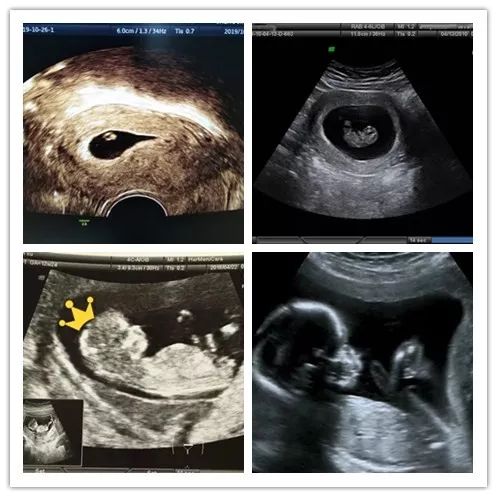

B超排除宫外孕

通过超声波检查,能看到胚囊在子宫内的位置,是否有卵黄囊,排除宫外孕。另外,还可以看到胚胎数目,以确定准妈妈是否孕育了双胞胎。

看胎心胎芽

通过超声波检查看胎芽,有无原始心管搏动。

这是很重要的早期系统超声检查,能够准确地估计孕周,校正预产期,检测NT厚度和鼻骨,有助于排查染色体异常。此时已进入相对稳定的阶段,医院会建议妈妈们尽快办理“围产保健手册”。